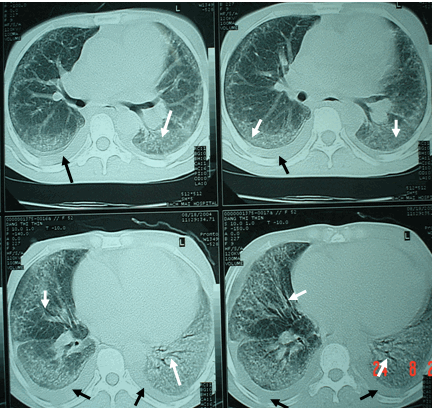

- Viêm phổi kẽ trên phim CT scaner

Viêm phổi kẽ trên phim CT scaner

Hình ảnh tràn dịch màng phổi (mũi tên đen) & hình ảnh kính mài - hội chứng đông đặc với các phế quản hơi (mũi tên trắng) trong viêm phổi kẽ được phát hiện trên phim chụp cắt lớp lồng ngực có độ phân giải cao